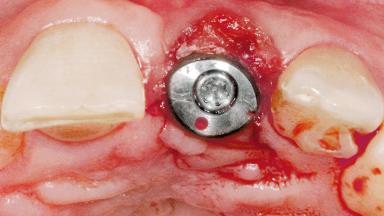

Late Flapless Placement of an Implant in a Maxillary Left Central Incisor Site

A 39-year-old male patient presented with a chief complaint of discomfort and gingival discoloration around his maxillary left central incisor. He was in good general health and was a non-smoker. His past dental history was significant because of the traumatic fracture of tooth 21 in a sporting accident at age 13. Initial dental treatment included endodontic therapy and a full-coverage restoration. The patient became symptomatic 5 years later, when structural failure of the tooth resulted in the dislodgment of the crown. Endodontic retreatment, apical surgery, and post-and-core restoration were performed.

Bone Augmentation Horizontal|Staged

Augmentation Materials Xenogenous|Membrane

Placement Protocol Early or late implant placement

Bone Volume Deficient horizontally, requiring prior grafting